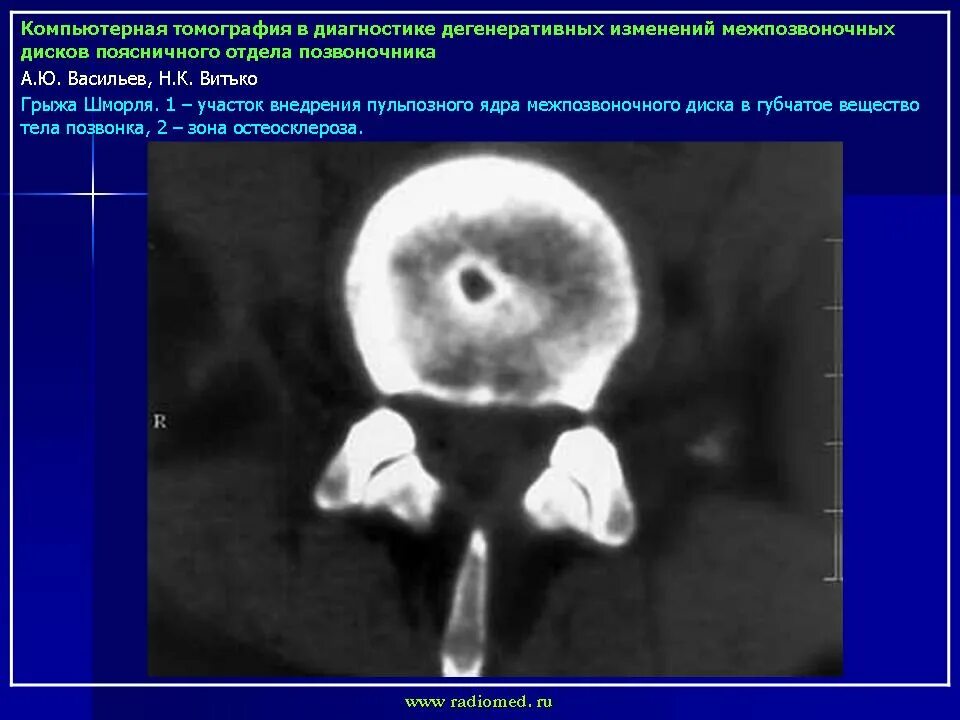

Мрт признаки дегенеративных изменений